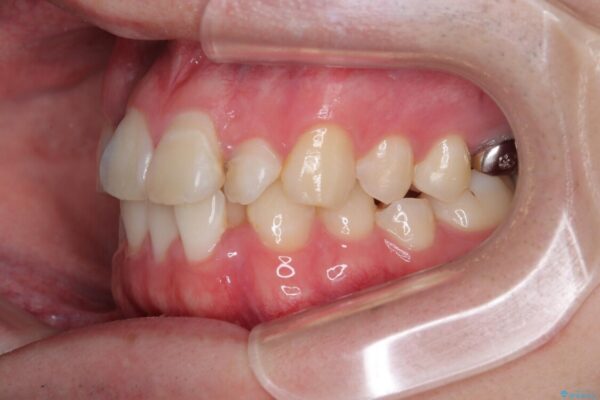

「歯並びがデコボコしていて、上下の中心がズレているのが気になる…」という悩みで来院された患者さまの症例をご紹介します。

初診時の状態

・上下ともに歯がきれいに並びきらず、がたつきが見られました。

・上下の前歯の中心(正中)がずれています。

・特に上顎の幅が狭いため、下顎の歯列も内側に入り込み、歯が並ぶスペースが不足していました。

治療前

• 1年でここまで変わる!歯列のがたつきと正中のズレを改善した矯正治療(メタルブラケット×MARPE) 治療前画像